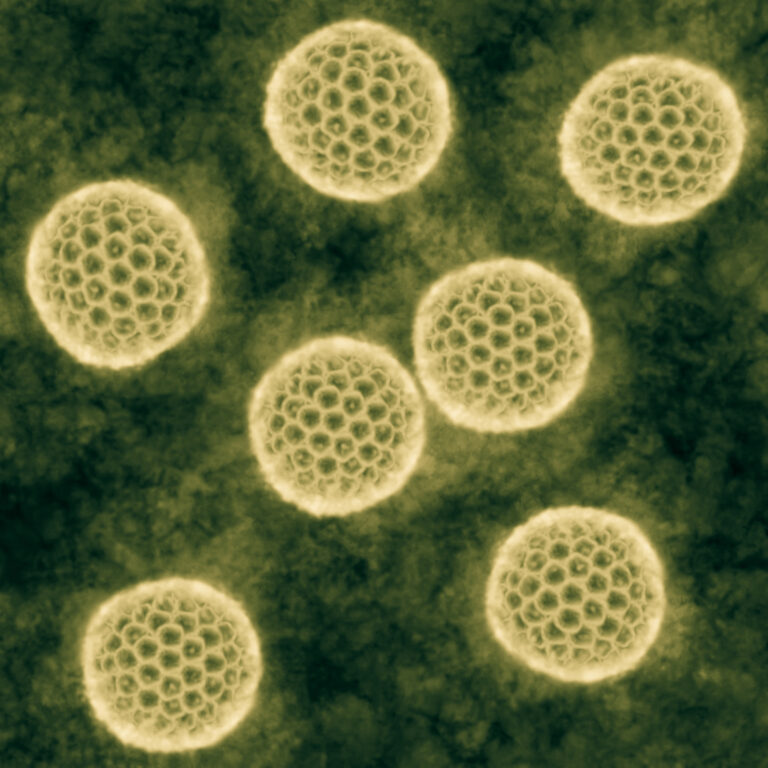

Pedrosa CDSG, Souza LRQ, Gomes TA, de Lima CVF, Ledur PF, Karmirian K, Barbeito-Andres J, Costa MDN, Higa LM, Rossi ÁD, Bellio M, Tanuri A, Prata-Barbosa A, Tovar-Moll F, Garcez PP, Lara FA, Molica RJR, Rehen SK. The cyanobacterial saxitoxin exacerbates neural cell death and brain malformations induced by Zika virus. PLoS Negl Trop Dis. 2020 Mar 12;14(3):e0008060.

Garcez PP, Loiola EC, Madeiro da Costa R, Higa LM, Trindade P, Delvecchio R, Nascimento JM, Brindeiro R, Tanuri A, Rehen SK. Zika virus impairs growth in human neurospheres and brain organoids. Science. 2016 May 13;352(6287):816-8.